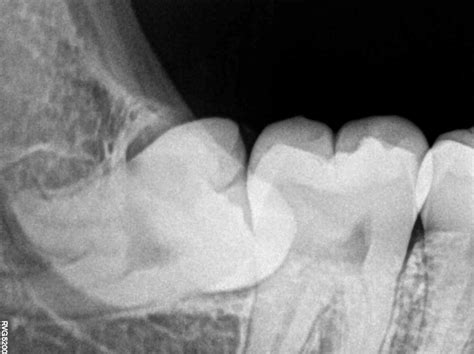

Assessment Clinical examination and dental X-rays to determine the position of the tooth.

The complexity of the extraction depends on whether the tooth has erupted or is fully impacted within the bone. An emergency dentist will assess the situation and perform the most conservative procedure necessary to resolve the acute issue immediately.